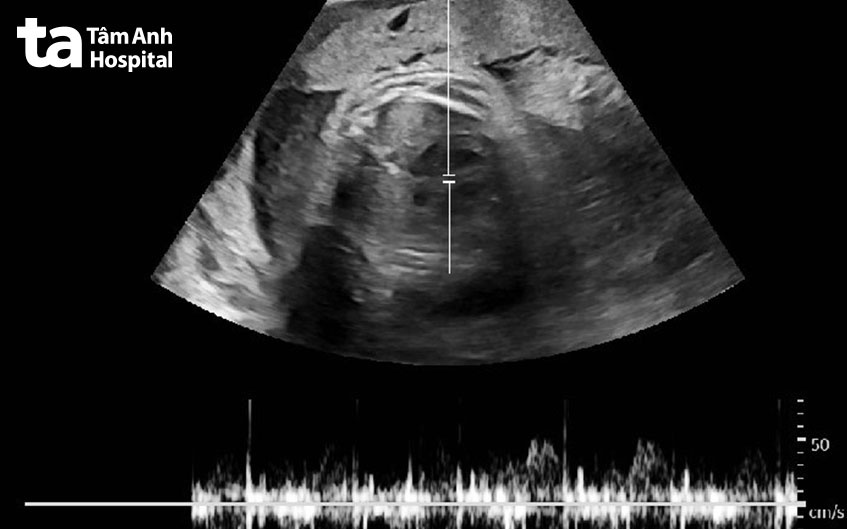

Chị Liên, 34 tuổi được người nhà đưa đến BVĐK Tâm Anh TP HCM cấp cứu vì mệt, khó thở. Bác sĩ kiểm tra huyết áp cao 185/120 mmHG (ở người bình thường chỉ số này là 120/80 mmHG), siêu âm tại giường thì bụng chị có bào thai sống, tương đương 34 tuần.

Ngày 1/7, BS.CKI Nguyễn Quang Nhật, Trung tâm Sản Phụ khoa cho biết, đây là trường hợp hy hữu biết mang thai muộn kèm theo dấu hiệu tiền sản giật, nguy cơ ảnh hưởng tính mạng được ghi nhận tại bệnh viện.